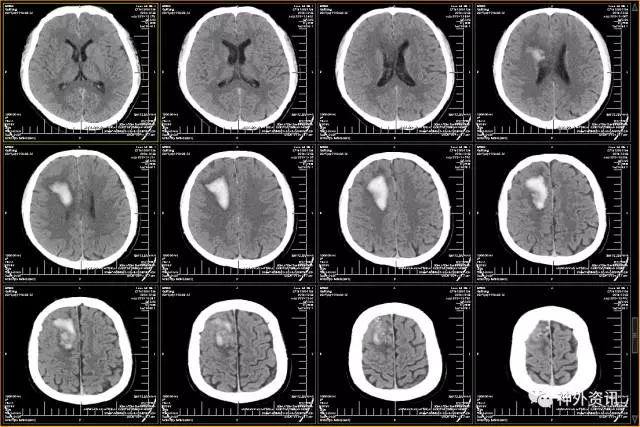

头颅CT示:蛛网膜下腔出血,脑干旁30mm*16mm占位,怀疑颅内动脉瘤可能。

脑动脉CTA示:左侧颞叶血肿,烟雾病伴血流相关性动脉瘤。

(头颅CT示:蛛网膜下腔出血,左侧颞叶血肿)

(增强CT:环池周围凌乱血管影伴瘤样扩张)